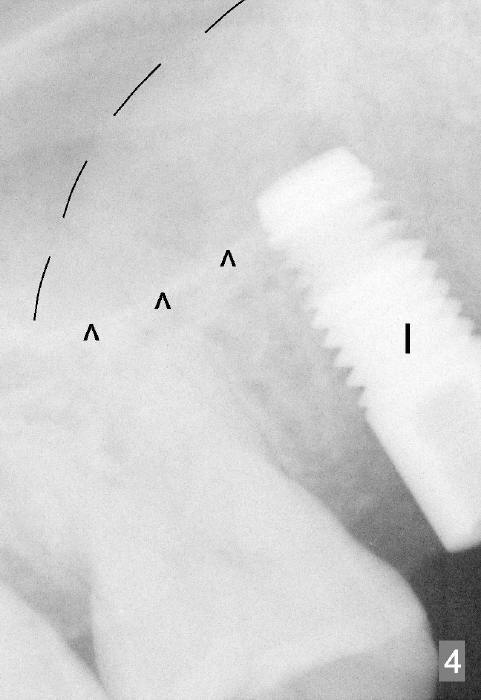

Osteotomes are used to form initial osteotomy, approximately 11 mm deep, 4 mm wide. Bicon reamers (Fig.3 R) are used to increase osteotomy while collecting autogenous bone; it appears that the sinus floor is partially penetrated (dashed line). After sinus lift (Fig.4 dashed line), a 5x14 mm cylindrical tissue-level implant is placed (I; arrowheads: sinus floor). There is no intraop nasal hemorrhage. Amoxicillin is prescribed postop (500 mg tid for 7 days). There is purulent, particulate discharge from the right nostril postop. One month later, the implant is loose and removed.